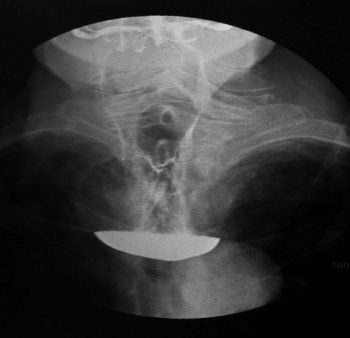

Figure 2: Barium study showing large pharyngeal pouch

Figure 2: Barium study showing large pharyngeal pouch(click to enlarge)

Flexiscope examination of the larynx and  hypopharynx was normal. Contrast radiography demonstrated a large pharyngeal pouch (see Figure 2).

Contrast studies rarely demonstrate a filling defect or loss of smooth contour of the interior of the pouch. In this case barium swallow showed a 4x6cm smooth-lined pouch with no suspicious radiological signs for malignancy.